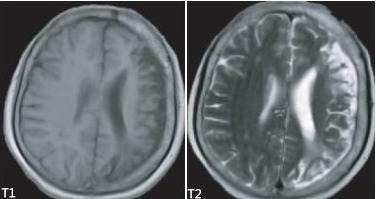

Dyke-Davidoff-Masson综合征

Dyke-Davidoff-Masson综合征是一种由于在胎儿期或生后早期脑损伤所致的少见病。

可发生于各年龄阶段如儿童、青少年及成人,男性发病率较高。

临床特征为癫痫、面部不对称、对侧偏瘫以及智力发育延迟,感觉障碍、学习及语言障碍、精神异常等表现也可出现。

影像表现为一侧大脑萎缩,同侧侧脑室扩张、颅骨增厚、鼻窦及乳突窦增大、岩骨嵴和蝶骨大翼抬升。